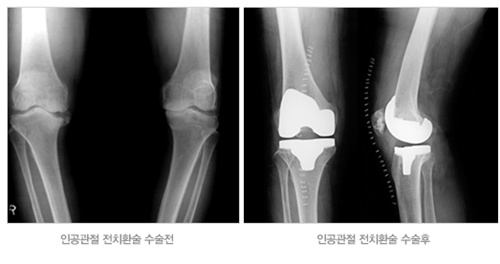

인공관절수술은 연골이 닳아서 움직일 때마다 심한 통증으로 인해 정상적인 생활을 할 수 없는 환자들이 최후의 수단으로 선택하게 되는 수술이다. 이는 통증의 치료뿐만 아니라 휘어진 다리를 곧게 해서 미용적인 효과와 심리적인 안정까지도 얻을 수 있다.

무릎인공관절 수술은 닳아 없어진 연골 대신 금속이나 세라믹으로 만들어진 인공관절로 대체하여 무릎의 통증을 없애주고, 정상적인 생활을 가능하게 한다.

인공관절 수술을 전문적으로 시행하고 있는 사랑의정형외과 국희균 원장은 “인공관절 수술은 관절의 통증을 감소시켜주는 효과와 더불어 보기 싫은 O자 다리를 교정해주고, 노년의 건강한 삶을 제공해주는 효과까지 있다. 또한 이제는 인공관절 수술이 많이 일반화되어 세라믹 인공관절, 여성형 인공관절, 부분 인공관절 등 환자에게 맞는 맞춤형 인공관절을 선택할 수 있을 만큼 의학이 많이 발전했다” 며 인공관절이 노년의 활동력 있는 삶을 제공해 줄 수 있는 매우 효과적인 방법이라고 설명했다. /생활경제팀 osenlife@osen.co.kr